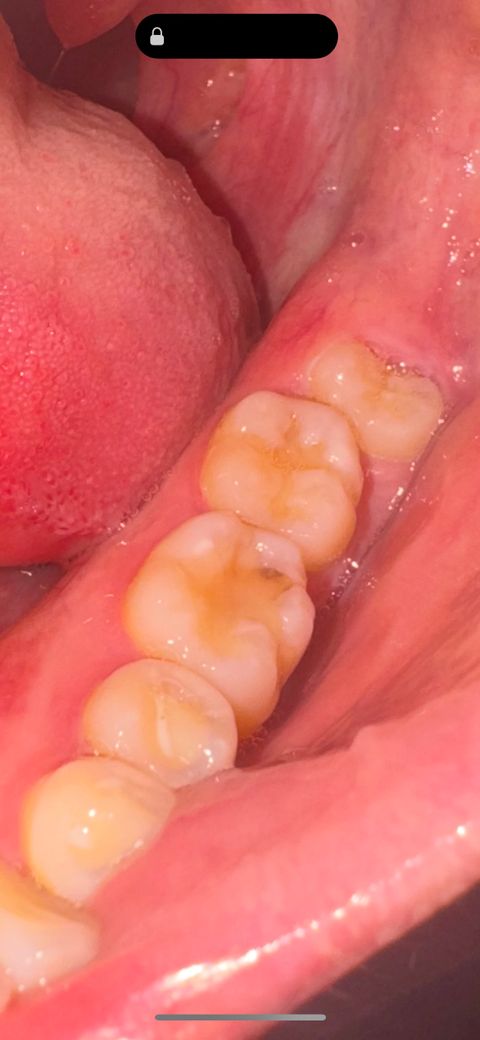

충치인가요? 레진 착색인가요? 알려주세요ㅠ

3개월전에 치과에 가서 정기검진 받을 땐 레진 착색이 있으니 좀만 더 써보고 레진 떼우자(?)라는 식으로 말씀하셨는데 오늘 다시보니 좀 까만거같은데 충치일까요?? 시리거나 통증은 아예없어요!!

기존에 치료를 햇던 레진주변으로 착색 및 2차 충치가 생긴거 같습니다. 치과에 가셔서 치료를 받으시는게 좋을것같습니다.

착색이 아니라 충치가 생긴 것으로 보입니다. 안쪽으로 진행된 것으로 보이니 치과에 가서 치료해야 할 것으로 보입니다.

사진으로 봤을땐 착색보다는 충치의 가능성도 있어보입니다 엑스레이 찍어볼 필요성은 있겠습니다

사진으로 봤을 때는 단순한 착색으로 보입니다 크게 문제가 되진 않을 것으로 생각되나 자세한 확인을 위해서는 치과에서 진료를 받아 보세요